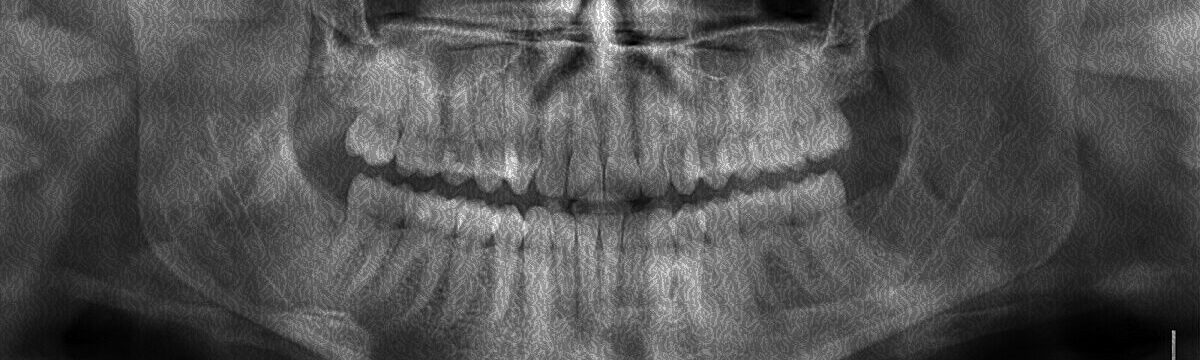

Jedním z dalších preventivních kroků by samozřejmě měla být pravidelná návštěva, a to nejen u zubního lékaře, ale i dentální hygienistky. Nejedná se však o rychlý pohled do vašich úst, profesionálové mohou včas zachytit problémy ještě, než se stanou vážnými. Kromě odstranění povlaku, zubního kamene či dalších nečistot, se během prohlídky kontroluje přítomnost zubního kazu, prvních známek onemocnění dásní nebo dokonce rakoviny dutiny ústní.